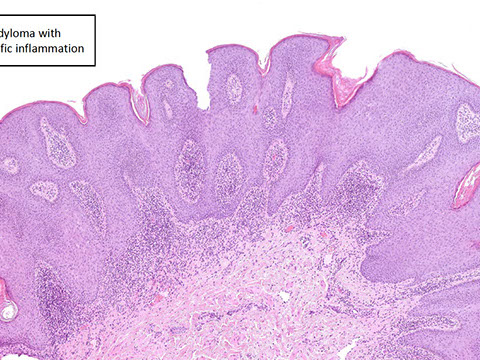

Cap polyposis

nflammatory cap polyp. This type of inflammatory pseudopolyp shows an overlying “cap” of necroinflammatory exudate. These polyps may occur in the setting of cap polyposis, at anastomotic sites, in association with inflammatory bowel disease (as in this case), or in many other conditions that induce mucosal ulceration. [2]